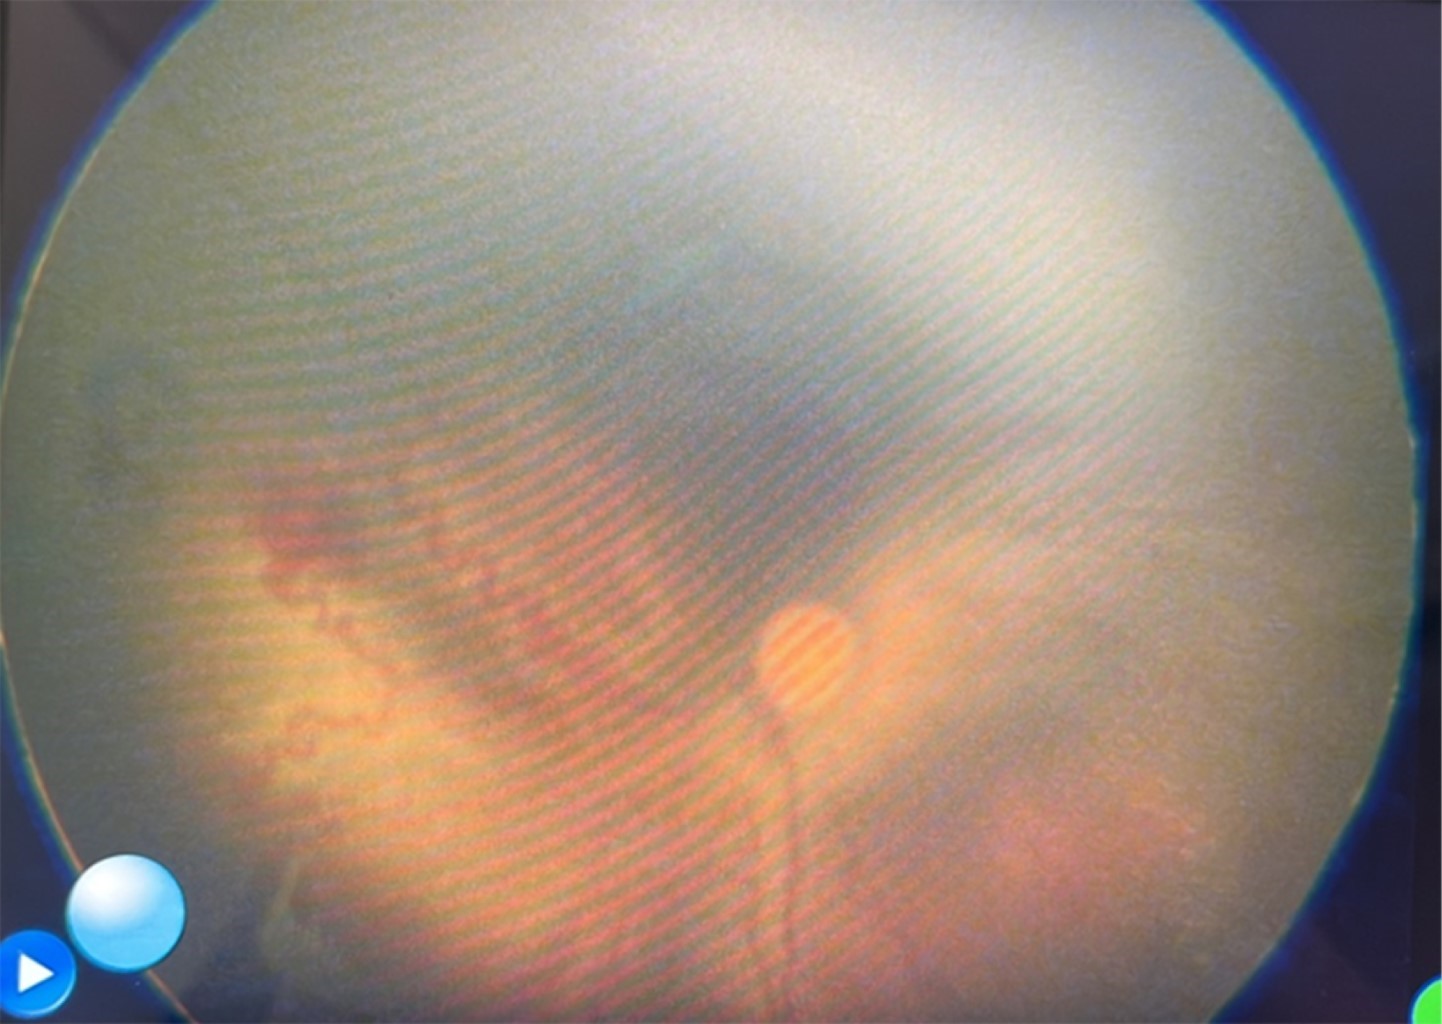

Visual screening: showing the world to newborns

visual screening, ocular screening, pediatric, wide field ocular fundus, retinopathy of prematurity.

The visual screening is the application of a simple, duplicable, valid, sensitive and specific test that allows identifying an ocular alteration that may not be evident at first glance during childhood and that is likely to cause visual or a systemic problem. In Mexico there is a legal basis to know when and who should go under this procedure, yet there is nothing to standardize the technique to be used. This paper describes the preliminary results of a visual screening model that allows to consider the usefulness and impact of an early visual screening since out of 50 screening babies, ten (20%) were found to carry visual problems that could be susceptible to correct in time but that puts vision at serious risk, causing permanent impairment, which implies not only suffering from the disease, but also negatively affects the family, the community and the country

Figure 1

Figure 2

Figure 3

Figure 4

Figure 5

Figure 6

Figure 7

Figure 8

Figure 9

Figure 10

Figure 11

Figure 12